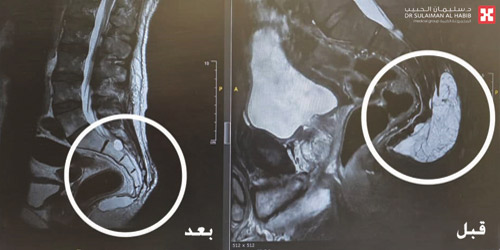

وقال د. مسعود إن الفحوصات الطبية والأشعة كشفت عن وجود كتلة ورمية كبيرة أسفل الظهر بحجم (9×7×10) سم، ضاغطة على أماكن تجمع الأعصاب والمسؤولة عن الإخراج والتبول. وأوضح أن الإجراء الجراحي لمثل هذه الحالة قد ينتج عنه إصابة أعصاب المثانة والبراز والمستقيم أثناء الاستئصال الكامل للورم، وما قد يترتب على ذلك من مضاعفات شديدة للمريض، لذا تم تكوين فريق طبي متخصص، وقرر الفريق ضرورة التدخل الجراحي العاجل لوضع حد لمعاناة المريض، مفيداً بأن العملية استغرقت 4 ساعات تحت التخدير العام، وتم فيها تحرير الورم من التصاقاته واستئصاله بشكل كامل دون أية مضاعفات، ونقل بعدها المريض إلى جناح التنويم.

وأكد د. مسعود أن جهود الفريق الطبي تكللت بالنجاح التام ولله الحمد، وخرج المريض من المستشفى بعد 3 أيام وهو بصحة جيدة، وقد انتهت لديه كافة الأعراض السابقة، مع تحسن مشكلة التشوه بمنطقة أسفل الظهر، وعاد ليمارس حياته الطبيعية.